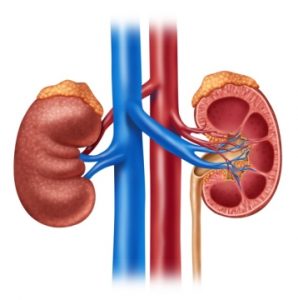

Tema: NyreneBeskrivelse: Tekst og oppgaver om nyrerNivå: Mellomtrinn Temat: NerkiOpis: Tekst i zadania dotyczące funkcjonowania i roli nerekPoziom: Klasy 5-7